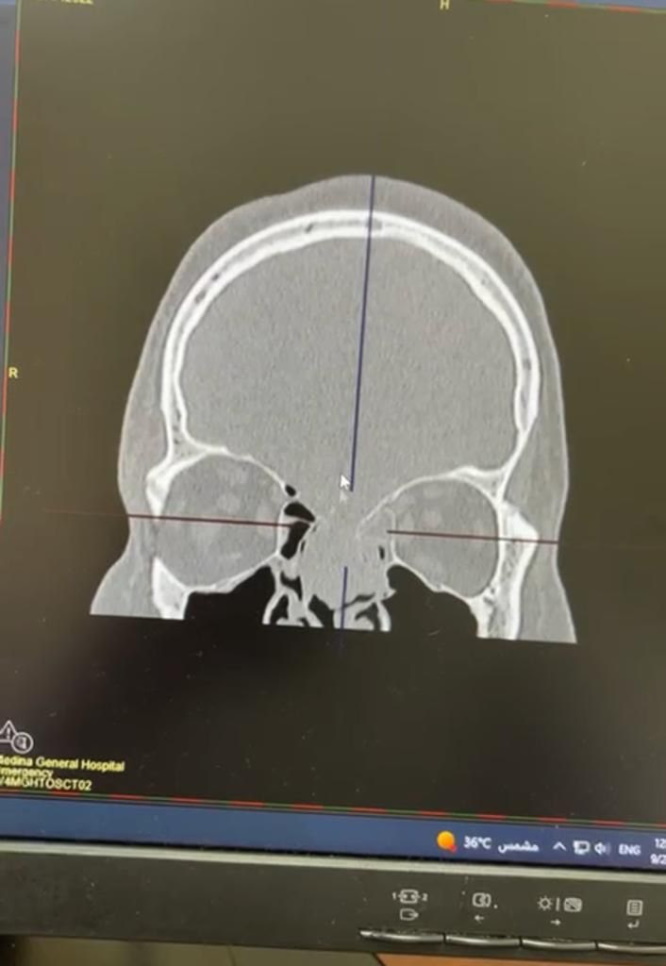

The Medina Health Assembly (western Saudi Arabia) confirmed that the patient came to the emergency department in a critical condition, semiconscious, and suffering from leakage of cerebrospinal fluid. Clinical examinations were immediately conducted that showed a gap in the base of the skull with swelling inside the cerebral ventricles.

Upon retrieval of his medical history, it was found that the patient had suffered from the consequences of an old traffic accident that led to a depression in the bottom of his skull, the condition developed due to the presence of a tumor within the ventricles of the brain, which led to a blockage and an increase in intracranial pressure.